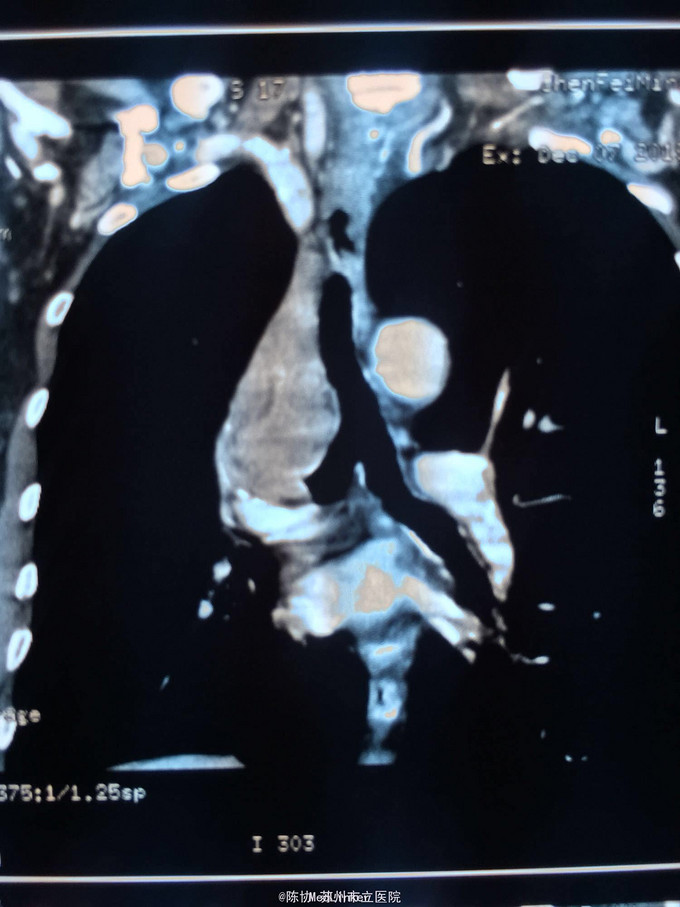

主诉:体检发现右上肺不张半月 77岁男,半月前体检发现右上肺不张,无不适。无消瘦,无咳血,无干咳。去年4月右上肺炎,抗生素治愈,当时CT未见肺肿块。入院支气管镜发现右上支气管开口组织增厚闭塞,开口近侧有隆起约3x3平方毫米,取活检5块病理示中度非典型增生。CT提示在右侧主支气管外侧有30x30平方毫米块影,压迫右上支气管开口处。三大常规和生化检查正常,肿瘤指标正常,TAP正常。

右侧中央型肺癌 重做支气管镜,精于定位找到病症组织,获得病理诊断来指导治疗。 胸外科医生不建议手术,理由是肿瘤位置靠近主支气管和气管,袖状切除不一定看干净。 请问正确的诊断,和比较合理的治疗方法是什么?求助大家思考评论